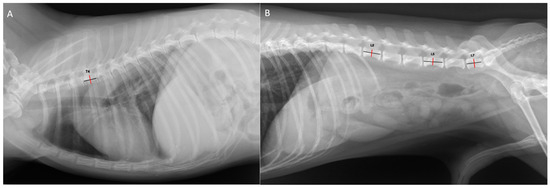

Radiographic Measurement and Evaluation